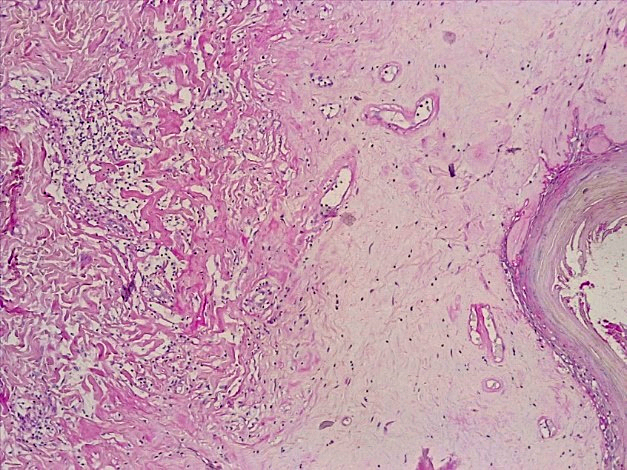

Что касается изменений со стороны дермы при атрофическом варианте СЛВ, то как в поверхностных, так и в глубоких слоях дермы отмечалось развитие плотной волокнистой соединительной ткани с лимфо-гистиоцитарной клеточной инфильтрацией, неравномерным ангиоматозом и кровенаполнением сосудов микроциркуляторного русла. При специальных окрасках на гликоген (ШИК-реакция по Хочкиссу) сосочковый слой в большинстве случаев был резко сглажен, замещен фиброзной соединительной тканью с признаками отека и гиалиноза за счет инфильтрации белковыми эозинофильными ШИК + массами (рис. 3), а в глубоких слоях кожи имелись признаки хронического воспаления разной степени выраженности за счет лимфо-плазмоцитарной и гистиоцитарной инфильтрации с отложением белковых скоплений гиалина.

Рис. 3. Атрофический вариант течения СЛ вульвы. Резкая атрофия эпидермиса с развитием выраженного фиброза поверхностных и глубоких слоев дермы. Умеренновыраженная лимфо-плазмоцитарная и гистиоцитарная инфильтрация стромы, выраженный ангиоматоз дермы, инфильтрация белковыми эозинофильными массами (ШИК-реакция по Хочкиссу, х100)

Fig. 3. Atrophic variant of the course of the vulva SL. Sharp atrophy of the epidermis with the development of pronounced fibrosis of the superficial and deep layers of the dermis. Moderate lymphoplasmocytic and histiocytic infiltration of the stroma, pronounced angiomatosis of the dermis, infiltration by protein eosinophilic masses (CHIC-Hotchkiss reaction, x 100)